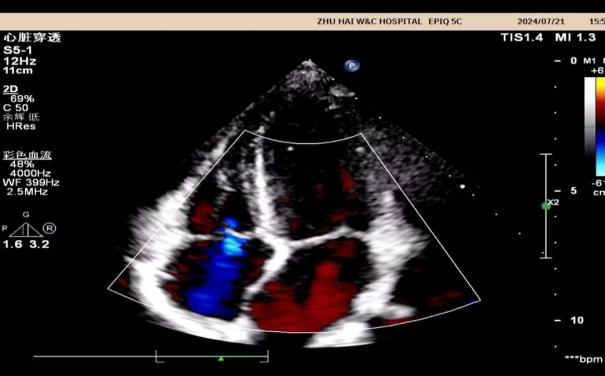

什么是心脏彩超?

心脏彩超是能够动态显示心腔内部结构、心脏搏动和血液流动情况的一种无创性检查技术。通俗地说,心脏探头有点类似于摄像机的镜头,通过镜头的不断移动和变换,让心脏的各个结构得到准确的呈现,从而让医生能够根据这些图像判断心脏是否存在问题。